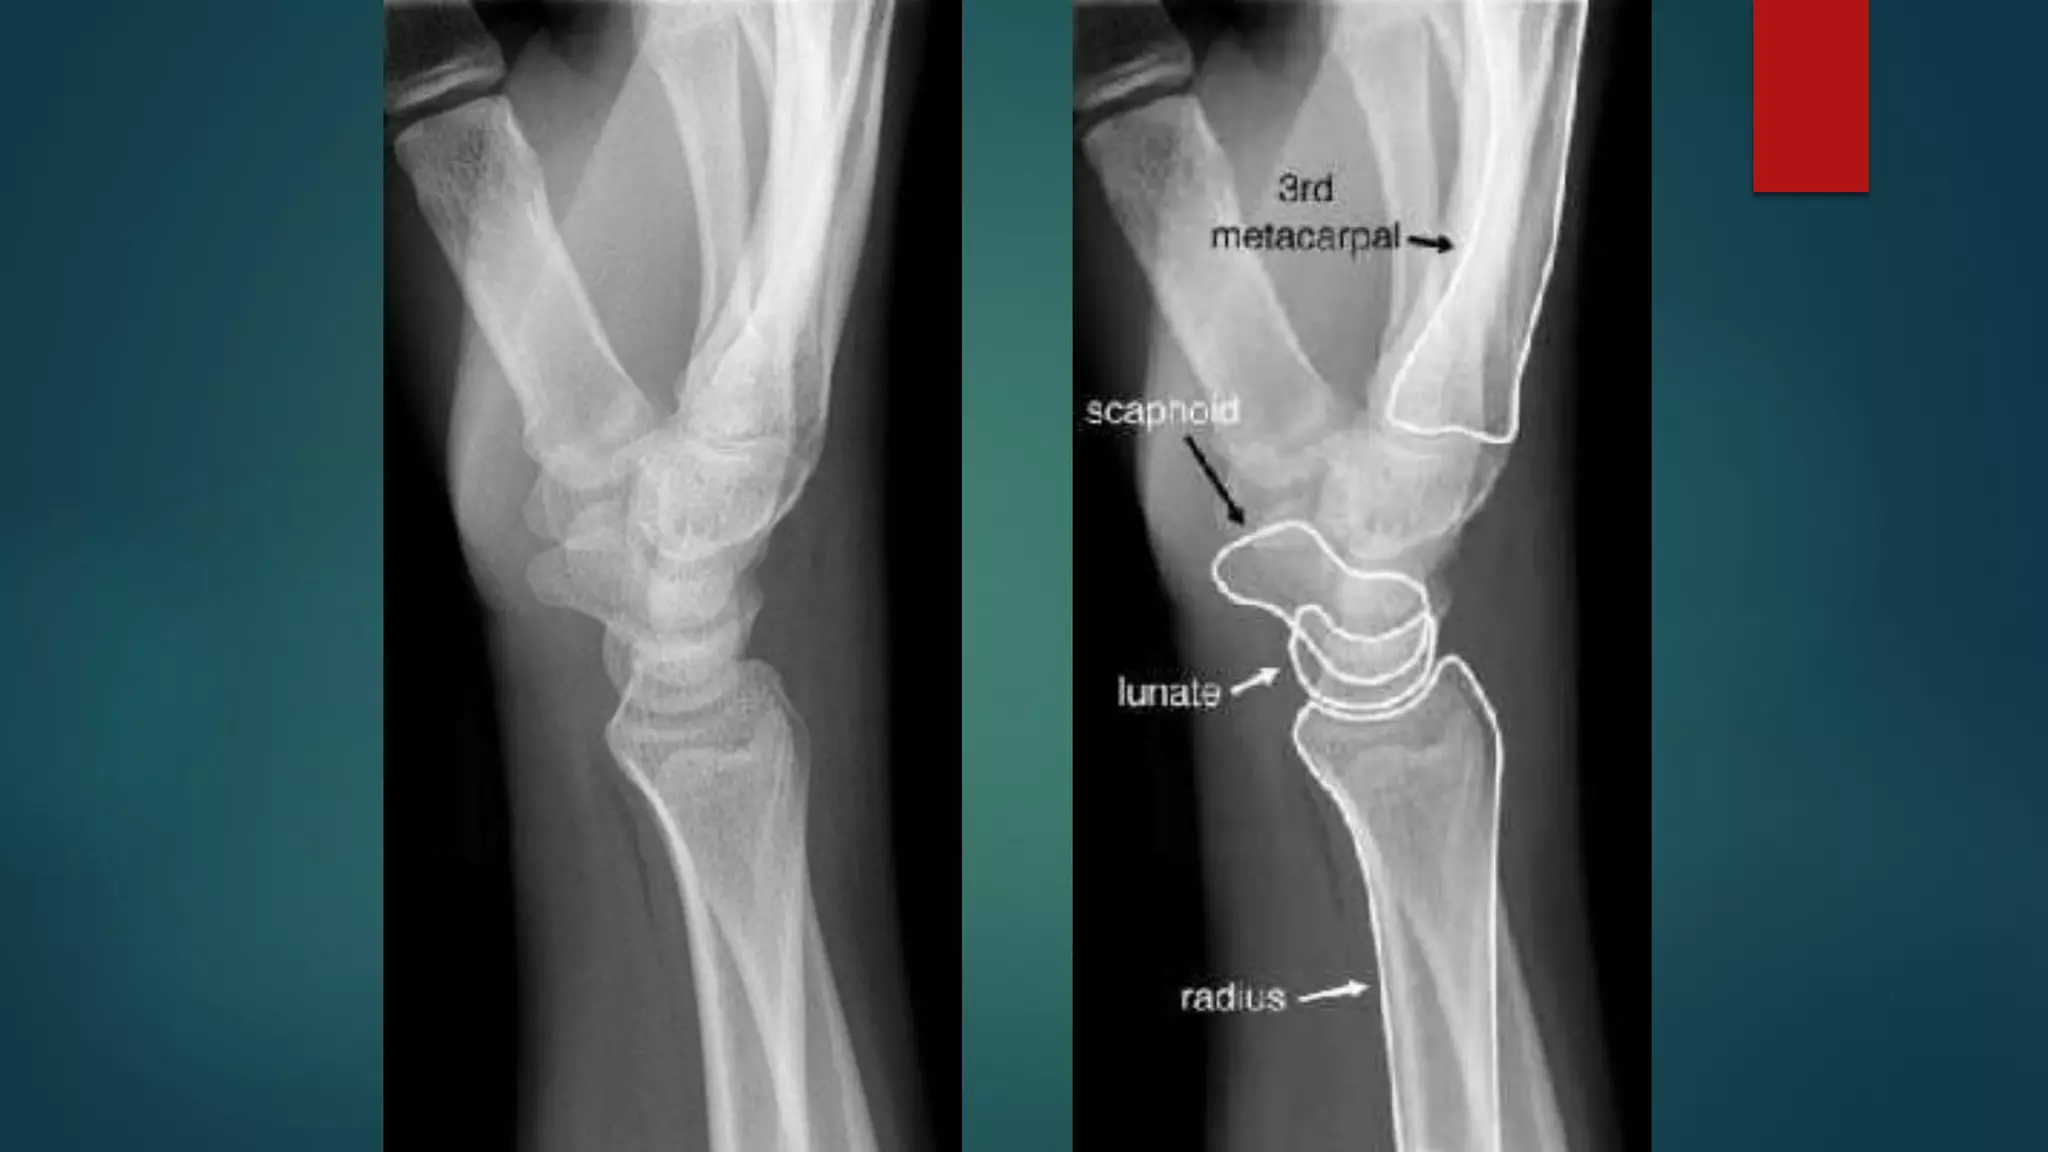

BONY ANATOMY

 Phalanges: 14

 Sesamoids: 2

 Metacarpals: 5

 Carpals

 Proximal row: 4

 Distal row: 4

 Radius and Ulna

BONY ANATOMY  Phalanges:14  Sesamoids: 2  Metacarpals: 5  Carpals  Proximal row: 4  Distal row: 4  Radius and Ulna